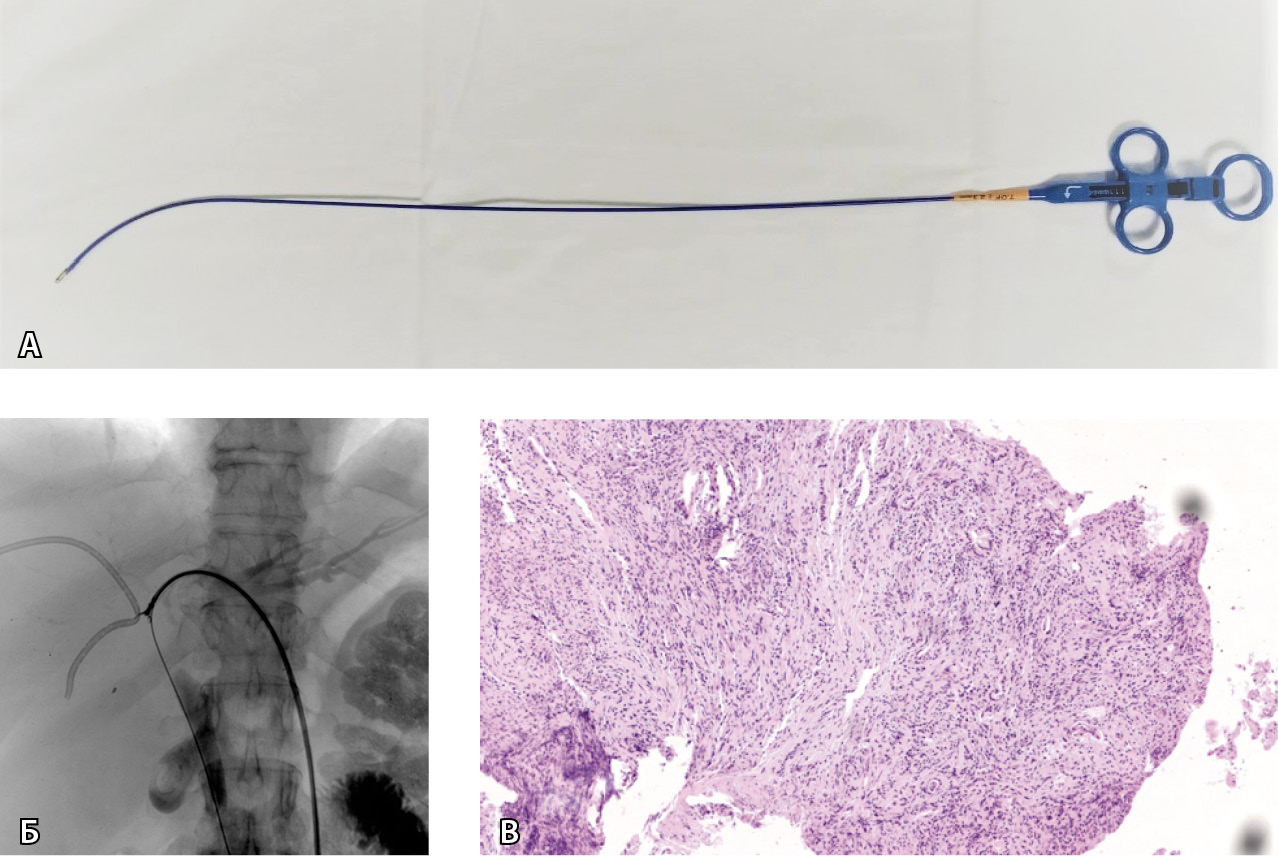

Процедуру заканчивали установкой билиарного дренажа в первоначальное положение для адекватного оттока желчи. После выполнения биопсии материал отправляли на морфологическое исследование (рис. 1).

Рис. 1. Щипковая биопсия у пациента с опухолью Клацкина, Bismuth IV. А – рентгеноконтрастные изгибаемые/вращающиеся биопсийные щипцы Cordis BIPAL 7 F (2,33 мм) длиной 50 см. Б – холангиография с последующей щипковой биопсией опухоли общего печеночного протока из левого доступа. Видны раскрытые бранши щипцов. В – биопсийный материал. Фрагмент стенки желчного протока с разрастанием низкодифференцированной аденокарциномы (окраска гематоксилином и эозином; × 6)